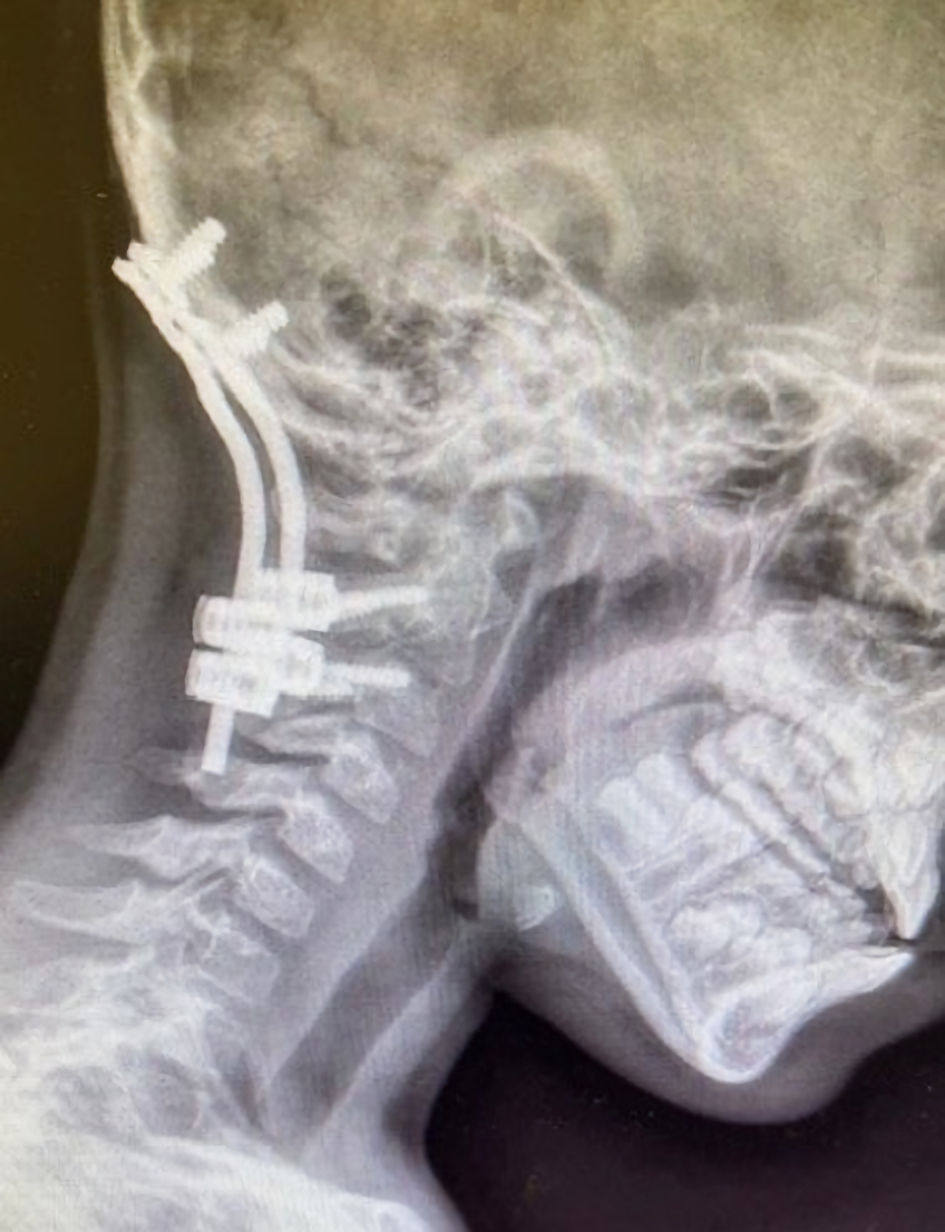

The fourth procedure was a left brachial plexus exploration and reconstruction with nerve grafting and direct intraoperative nerve stimulation to assess muscle responses. The complexity of this case relied on preserving neuromuscular function for reliable nerve stimulation while ensuring cervical spine and airway protection. Perioperative vital signs showed a temperature of 37.2 °C (99 °F), pulse 109 beats/min, blood pressure 102/77 mm Hg, and oxygen saturation of 100% on room air. On physical examination, there was limited neck flexion and extension, as well as the past history of airway concerns and the previous cervical fusion and instrumentation (Fig. 3). Cardiac and respiratory examinations were otherwise unremarkable. The patient was held nil per os (NPO) for 8 h before the surgery. Routine American Society of Anesthesiologists monitors were applied, and anesthesia was induced by the inhalation of sevoflurane (8%) in oxygen. A peripheral IV cannula was placed after achieving adequate depth of anesthesia, followed by an IV bolus of propofol (4 mg/kg) and fentanyl (2.5 µg/kg). Bag-mask ventilation was confirmed to be easy, and the patient’s trachea was intubated 2 min later using videolaryngoscopy (Glidescope, LowPro blade size 2.5), yielding a Cormack–Lehane grade I view and allowing successful placement of a 5.0-mm cuffed ETT assisted by a bougie. Placement was confirmed with capnography, chest rise, and bilateral breath sounds. To facilitate muscle responses during intraoperative nerve stimulation, neuromuscular blocking agents (NMBAs) were avoided. Maintenance anesthesia consisted of sevoflurane (2%), remifentanil infusion (0.1–0.3 µg/kg/min), and supplemental IV boluses of fentanyl (1 µg/kg), hydromorphone (0.015 mg/kg), dexamethasone (0.3 mg/kg), and acetaminophen (15 mg/kg). Ondansetron (0.1 mg/kg) was administered for nausea prophylaxis, and cefazolin (50 mg/kg every 3 h) was given to prevent surgical site infections. A total volume of 627 mL of lactated Ringer’s solution was administered during 8 h of anesthetic care. The patient’s trachea was extubated in the OR when fully awake, and she was transferred to the post-anesthesia care unit (PACU) in stable hemodynamic condition. The patient was discharged home on POD 1. A wide range of cervical spine precautions were applied during each anesthetic encounter, and further details regarding our observations and management are described below.

Click for large image

Figure 3. Preoperative radiographs demonstrating cervical spine instrumentation for stabilization following atlanto-occipital dislocation.